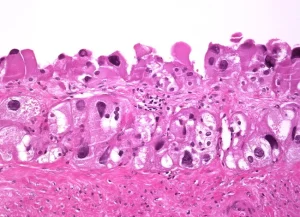

- Foliküler Kist: Yumurtlama sırasında folikül yeterince olgunlaşmadığında, sıvı dolu kist haline gelir. Genellikle birkaç hafta içinde kaybolur.